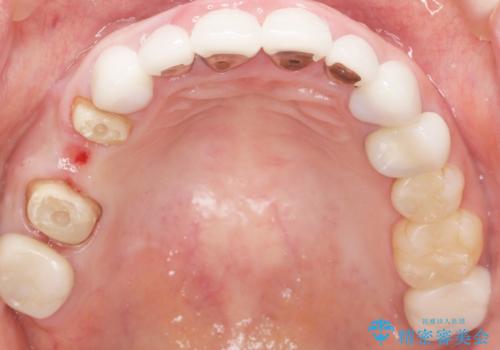

- 被せ物と歯ぐきの境目が黒いことを気にされ、来院された患者様です。

精査したところ、メタルボンドクラウンの金属部分が露出し黒く見えていました。

患者様のご希望により、金属を使わないオールセラミックのブリッジによる補綴治療を行いました。

金属の土台も除去し、ファイバーコア(金属を使わない強度のあるしなやかな土台)へやりかえました。

- ¥407,000 (仮歯・クラウン×3本、土台×2本) ※税込費用は治療当時の料金となります